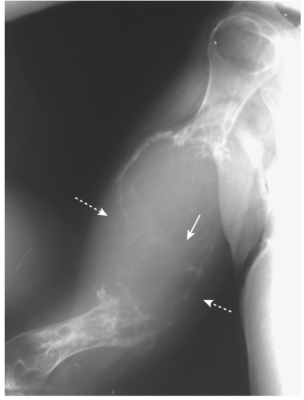

- Ăn mòn đầu xa xương đòn (Hình -3)